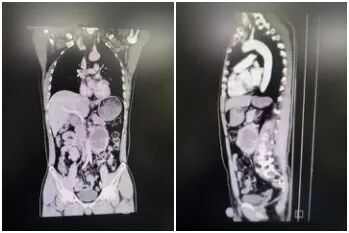

49岁的柳先生因不明原因高血压、头疼、晕厥辗转入住市一医院泌尿外科,腹部ct检查提示左侧肾上腺11.7×*5.6cm占位,这让他感到特别焦虑,严重影响生活和工作。异位嗜铬细胞瘤(PGL)是起源于肾上腺外交感神经链的肿瘤,为临床少见内分泌疾病,大于5cm的异位巨大肿瘤病例更是非常罕见。因肿瘤合成分泌大量儿茶酚胺引起患者阵发性高血压,可导致严重的心脑肾并发症。该肿瘤首选手术切除,但术中术后血压容易剧烈波动,手术风险极高。

3月24日,在制定周祥的手术方案、进行积极扩容等充分术前准备后,手术按计划进行。术中可见巨大肿物位于左侧中腹部腹主动脉前方,最大直径约12cm,包膜薄,肿瘤与周围组织和血管严重粘连,术中轻微触碰肿瘤即可引起血压飙升,同时,稍有损伤即可导致大动脉破裂。无疑,这是又一次极高的挑战。在麻醉医师严密监测及积极控制下,李斌主任、杜晓博副主任等泌外科精英团队全神贯注、精细分离粘连的肠管、胰腺和血管,历时4个半小时,终于顺利将肿物完整切除。